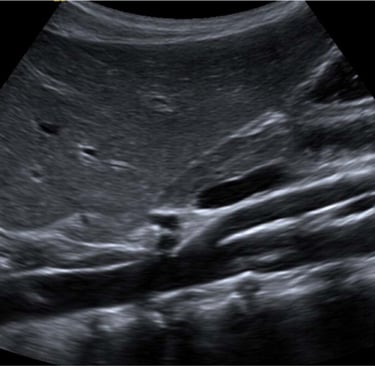

An abdominal aortic ultrasound is a non-invasive imaging test that uses sound waves to evaluate the aorta — the main blood vessel that carries blood from your heart to the rest of your body. The exam focuses on the portion of the aorta that passes through the abdomen.

This test is commonly performed to detect an abdominal aortic aneurysm (AAA) — a dangerous enlargement or bulging of the aorta that can lead to life-threatening complications if not found early.

The sonographer will move a small probe (transducer) over your skin to capture images of the aorta.